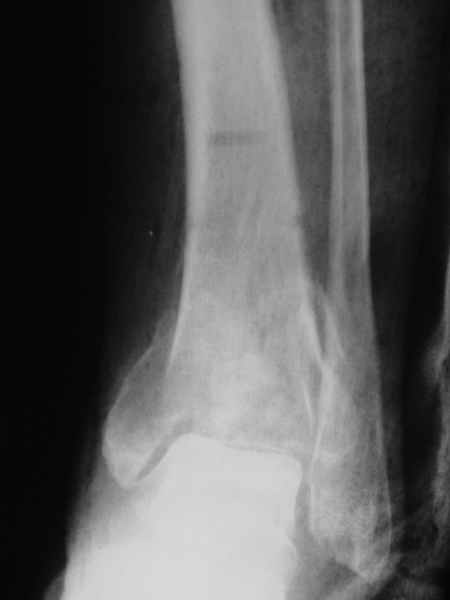

Female. 65 years old. 2 years ago trimalleolar fracture left ankle. First ORIF failed. Second ORIF with autologous graft at the fibular fracture was complicated by infection. The X-ray pictures show the actual situation. What are the suggestions of the group?